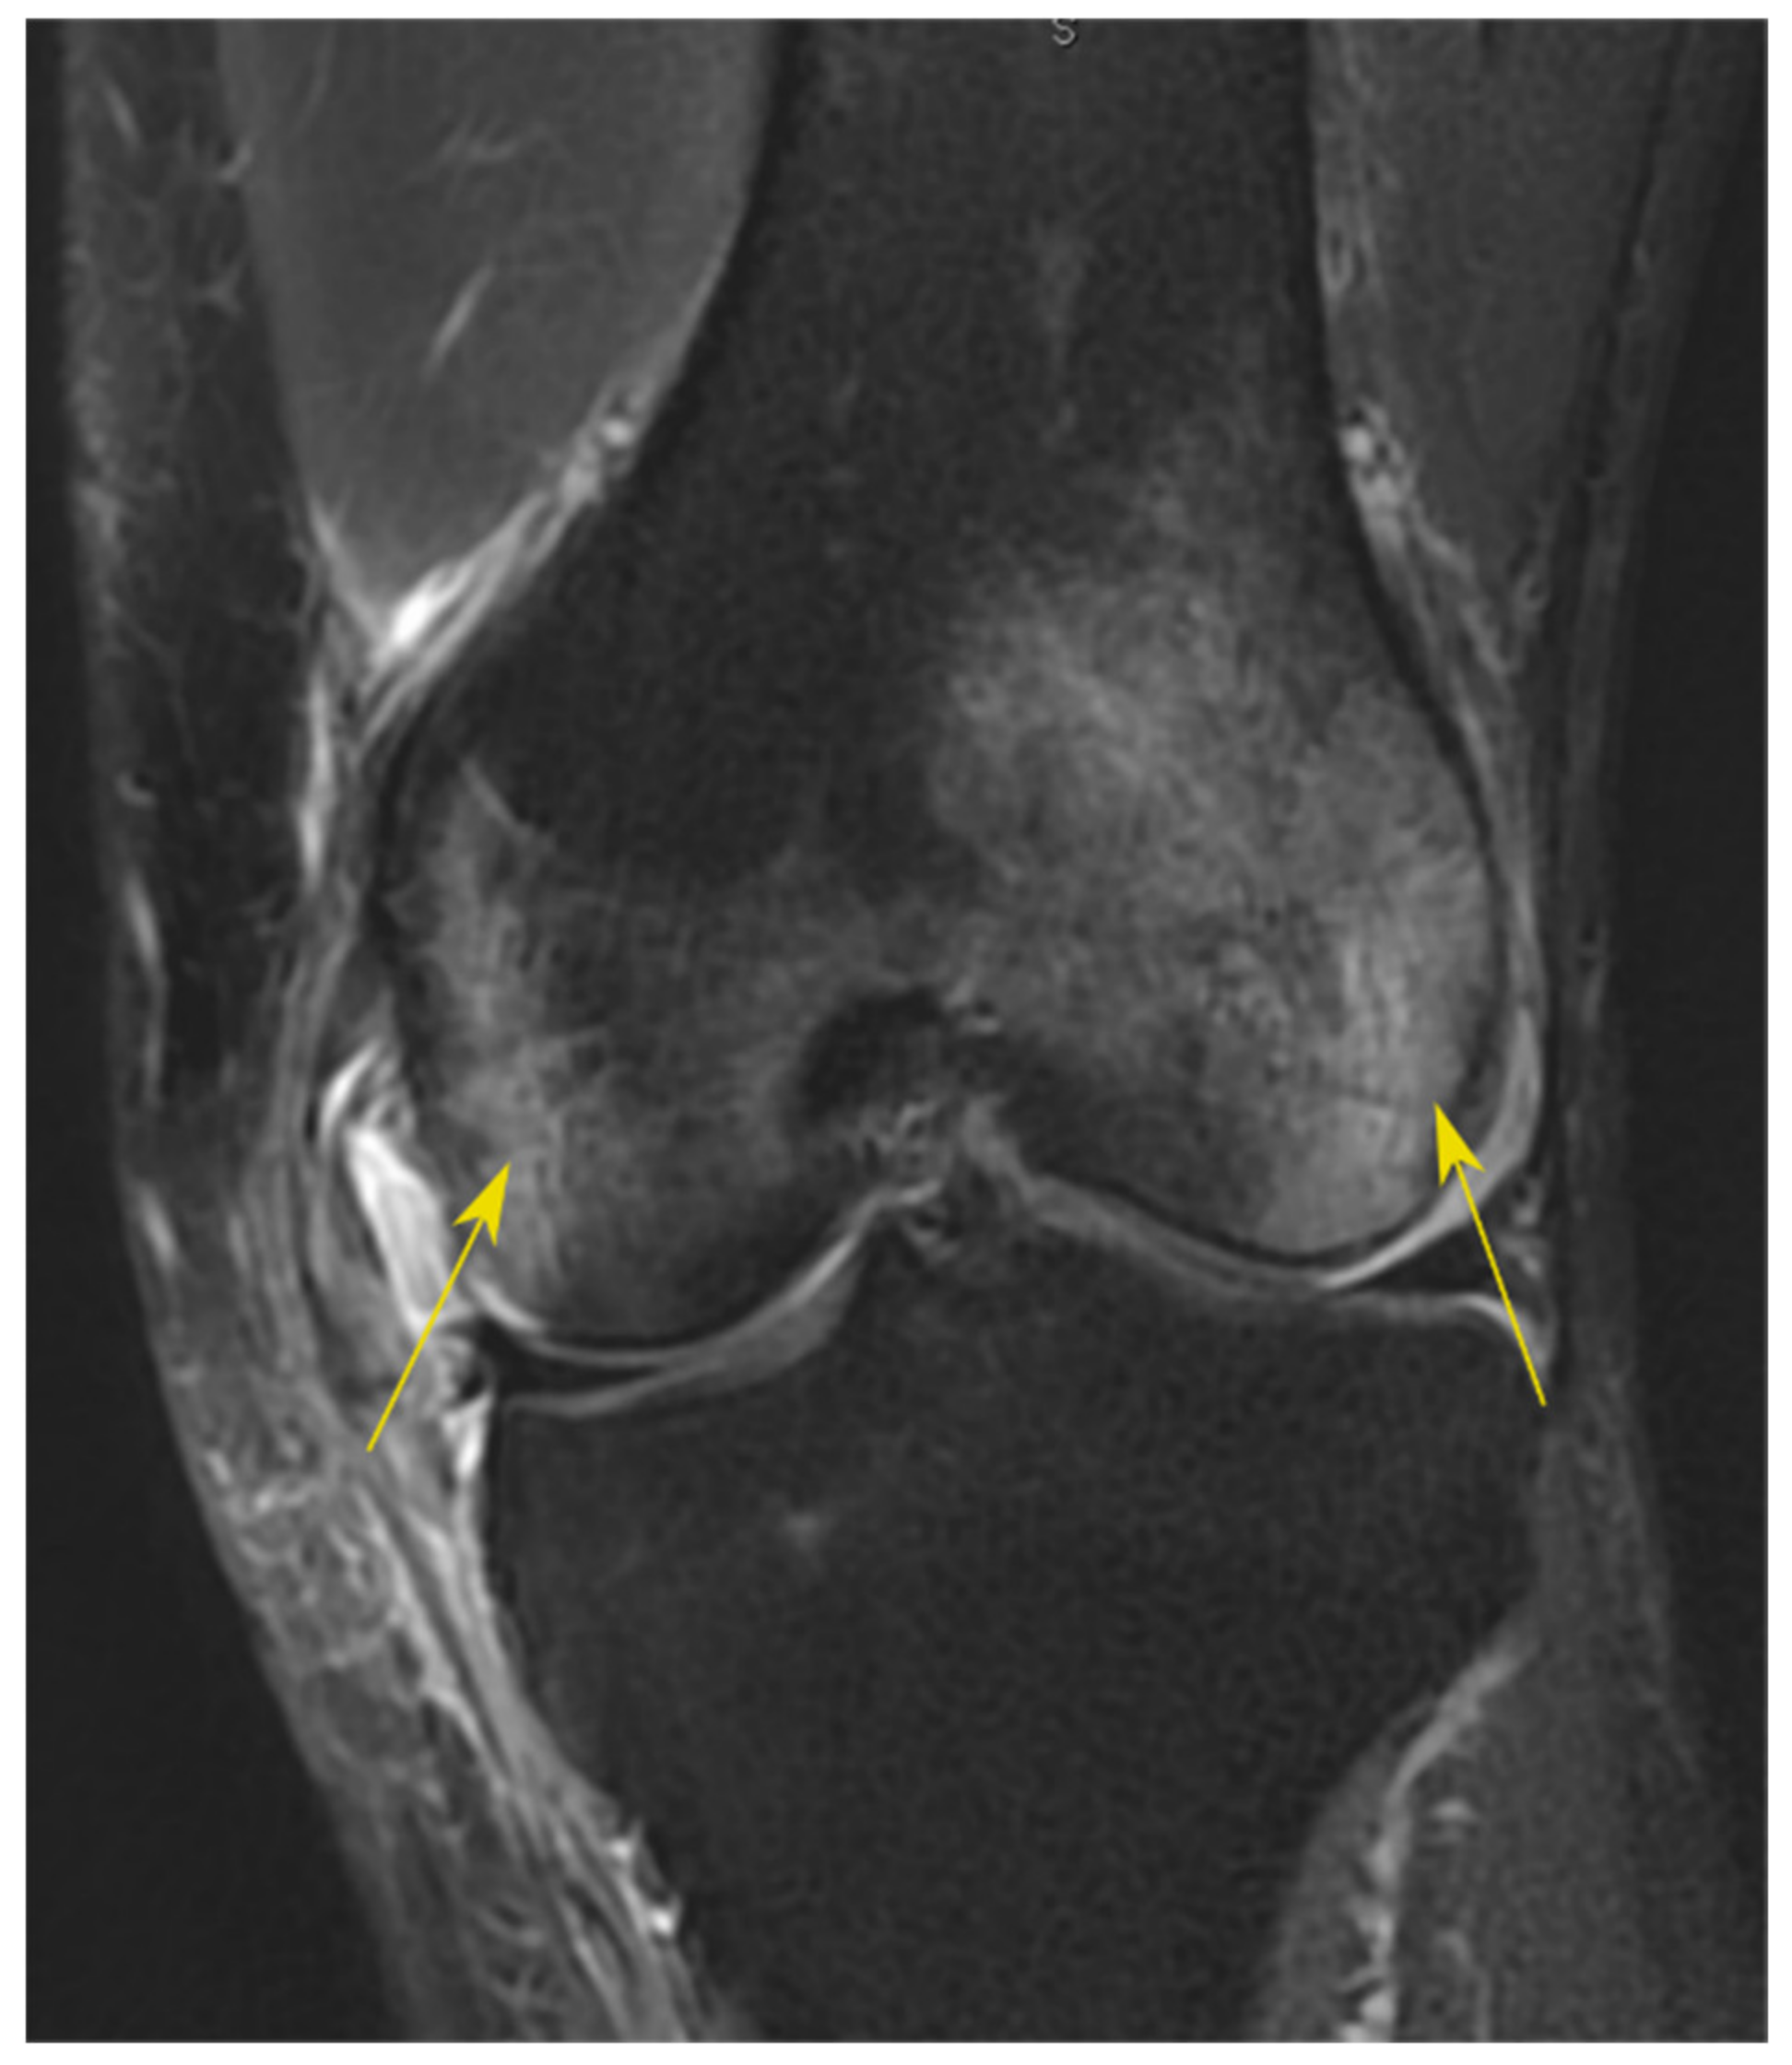

2.1. Measurements of Bone Bruises

- Patel, S.A.; Hageman, J.; Quatman, C.E.; Wordeman, S.C.; Hewett, T.E. Prevalence and Location of Bone Bruises Associated with Anterior Cruciate Ligament Injury and Implications for Mechanism of Injury: A Systematic Review. Sports Med. 2014, 44, 281–293. [Google Scholar] [CrossRef]

- Sanders, T.G.; Medynski, M.A.; Feller, J.F.; Lawhorn, K.W. Bone Contusion Patterns of the Knee at MR Imaging: Footprint of the Mechanism of Injury. RadioGraphics 2000, 20, S135–S151. [Google Scholar] [CrossRef] [PubMed]

- Speer, K.P.; Spritzer, C.E.; Bassett, F.H.; Feagin, J.J.A.; Garrett, J.W.E. Osseous injury associated with acute tears of the anterior cruciate ligament. Am. J. Sports Med. 1992, 20, 382–389. [Google Scholar] [CrossRef] [PubMed]